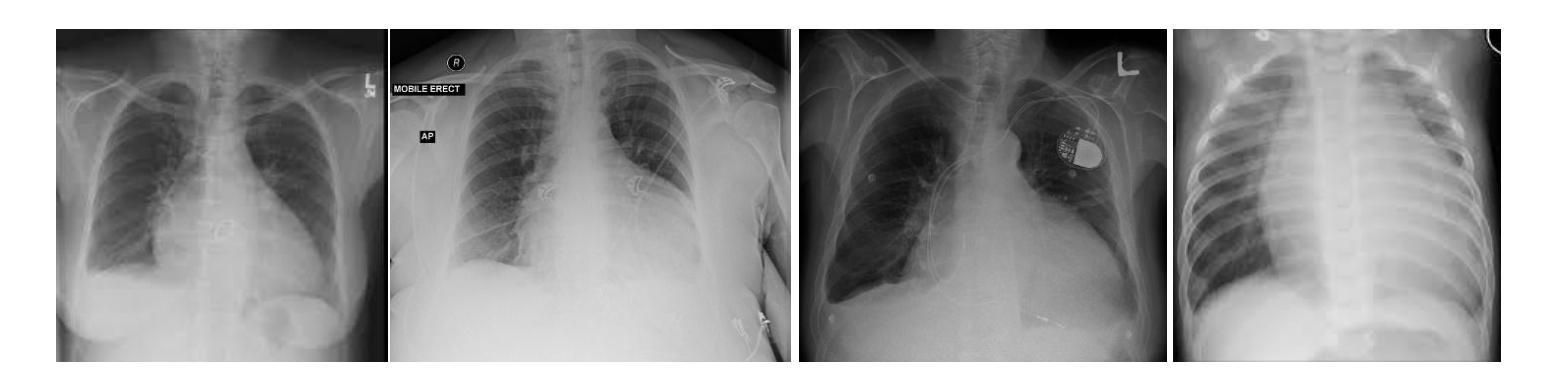

Multi Head Attention Enhanced Inception v3 for Cardiomegaly Detection

Authors:Abishek Karthik, Pandiyaraju V

The healthcare industry has been revolutionized significantly by novel imaging technologies, not just in the diagnosis of cardiovascular diseases but also by the visualization of structural abnormalities like cardiomegaly. This article explains an integrated approach to the use of deep learning tools and attention mechanisms for automatic detection of cardiomegaly using X-ray images. The initiation of the project is grounded on a strong Data Collection phase and gathering the data of annotated X-ray images of various types. Then, while the Preprocessing module fine-tunes image quality, it is feasible to utilize the best out of the data quality in the proposed system. In our proposed system, the process is a CNN configuration leveraging the inception V3 model as one of the key blocks. Besides, we also employ a multilayer attention mechanism to enhance the strength. The most important feature of the method is the multi-head attention mechanism that can learn features automatically. By exact selective focusing on only some regions of input, the model can thus identify cardiomegaly in a sensitive manner. Attention rating is calculated, duplicated, and applied to enhance representation of main data, and therefore there is a successful diagnosis. The Evaluation stage will be extremely strict and it will thoroughly evaluate the model based on such measures as accuracy and precision. This will validate that the model can identify cardiomegaly and will also show the clinical significance of this method. The model has accuracy of 95.6, precision of 95.2, recall of 96.2, sensitivity of 95.7, specificity of 96.1 and an Area Under Curve(AUC) of 96.0 and their respective graphs are plotted for visualisation.

医疗健康行业被新型成像技术彻底革新,这不仅体现在心血管疾病的诊断上,还体现在诸如心脏增大等结构异常的可视化上。本文介绍了一种利用深度学习工具和注意力机制自动检测心脏增大的X射线图像的综合方法。该项目的启动基于强大的数据采集阶段和收集各种已标注的X射线图像数据。然后,预处理模块对图像质量进行微调,以便在拟议系统中充分利用数据质量。在我们提出的系统中,过程是一个利用inception V3模型作为关键模块之一的CNN配置。此外,我们还采用多层注意力机制来提升强度。该方法最重要的特点是多头注意力机制,它可以自动学习特征。通过精确选择仅聚焦在某些输入区域上,该模型能够以敏感的方式识别心脏增大。计算注意力评分,对其进行复制并应用于增强主数据的表示,从而进行成功的诊断。评估阶段将非常严格,它将根据准确性、精确度等指标对模型进行全面评估。这将验证模型识别心脏增大的能力,并显示该方法的临床意义。该模型的准确度为95.6%,精确度为95.2%,召回率为96.2%,灵敏度为95.7%,特异度为96.1%,曲线下面积(AUC)为92.0,并绘制了相应的图表用于可视化展示。

Summary

本文介绍了一种利用深度学习工具和注意力机制自动检测心胸增大(Cardiomegaly)的方法。该方法采用集成方案,基于强数据采集阶段进行数据收集并利用预处理器优化图像质量。使用卷积神经网络配置,采用inception V3模型作为关键模块之一,并采用多层注意力机制提升效能。最重要的特点是采用多头注意力机制可自动学习特征。通过对输入数据的精确选择性关注,该模型可以灵敏地识别心胸增大。该方法已成功应用于诊断阶段,其准确性得到验证。模型的准确度为95.6%,精确度、召回率等指标均表现良好,且已绘制相应的图表进行可视化展示。

Key Takeaways

1. 新一代成像技术为医疗保健行业带来重大变革,不仅在心血管疾病诊断中,还能通过可视化结构性异常(如心胸增大)辅助诊断。

2. 文章介绍了一种结合深度学习工具和注意力机制的自动检测心胸增大的方法,使用X射线图像。

3. 项目的启动基于强大的数据采集阶段,收集各种类型的带注释的X射线图像数据。

4. 在预处理模块中优化了图像质量,以便在提出的系统中充分利用数据质量。

5. 采用卷积神经网络配置,包括inception V3模型作为关键组成部分,并使用了多层注意力机制以增强效能。

6. 多头注意力机制是该方法最重要的特点,可自动学习特征,并通过精确选择性关注输入数据来识别心胸增大。

Cool Papers